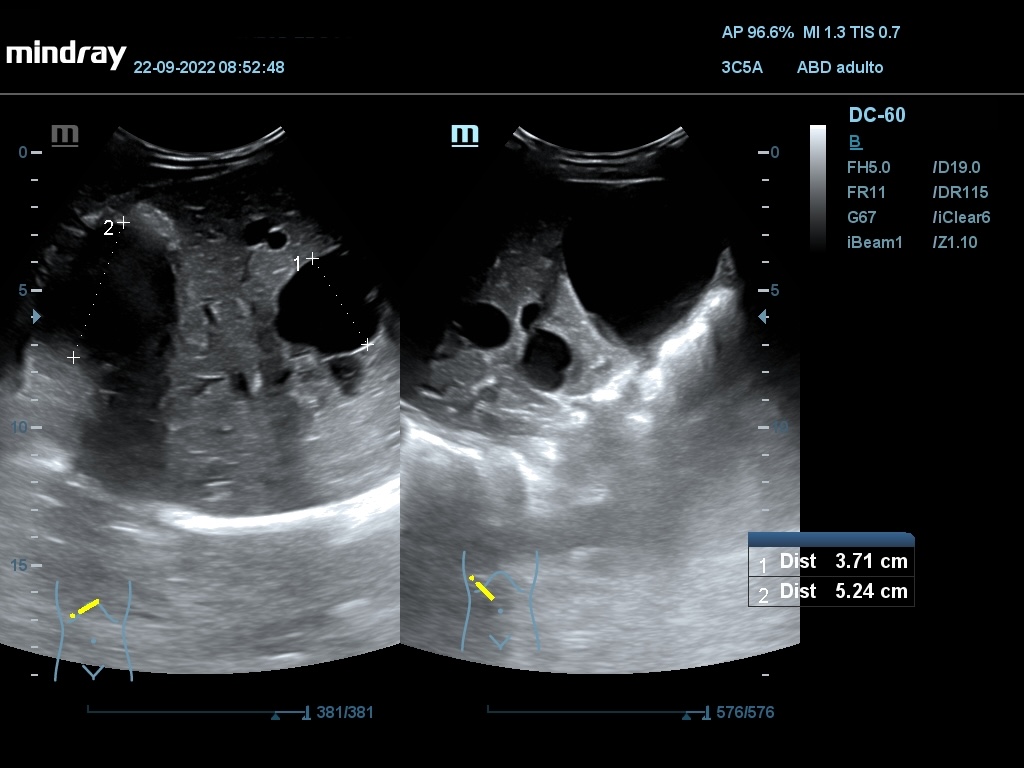

Ecografía abdominal: Se observan varios quistes simples a nivel hepático, siendo el mayor de 52,4 mm, en ambos riñones siendo el mayor de 77 x 83 mm en RD y de 80 x 64 mm en RI. En hipogastrio se observa imagen redondeada, anecogénica, con sombra posterior, de borde liso y fino, no tabicada, de aprox. 161 x 142 mm y otra de características similares de 74 x 54 mm.